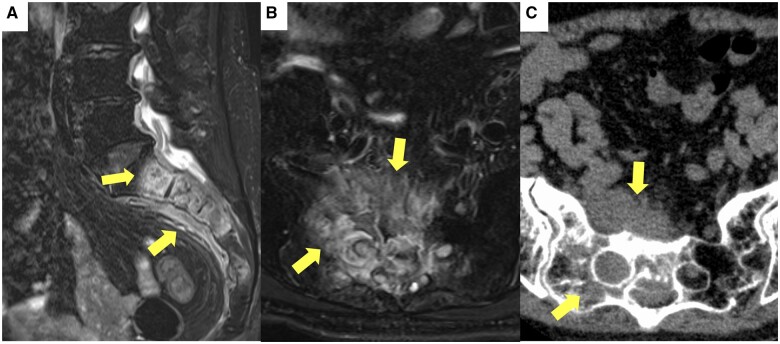

Methotrexate (MTX) is a drug used for treating rheumatoid arthritis. Recently, the reported incidence of methotrexate-associated lymphoproliferative disease (MTX-LPD) has increased, especially in Japan. Extranodal involvement is observed in half of MTX-LPD cases. However, only a few spinal lesions have been reported, with none in the sacrum. Additionally, Epstein-Barr virus (EBV) infection has also been implicated in the pathogenesis of MTX-LPD. Herein, we describe the case of a 74-year-old woman with MTX-LPD in the sacral spine who complained of severe back pain and nocturnal pain. Radiographs revealed a tumour on the right wing of the sacrum and a positive EBV immunoglobulin G antibody titre. MTX-LPD was suspected based on imaging findings and a history of MTX administration. A pathological examination was performed on the CT-guided biopsy specimen. The histopathological diagnosis was MTX-LPD, and MTX was discontinued. Three months after MTX administration ended, the tumour tended to shrink, and 1 year later, significant tumour shrinkage was observed. This experience suggests that MTX-LPD can be treated by discontinuing MTX administration. Therefore, early and accurate diagnosis is required, as is avoiding unnecessary treatment such as surgery. MTX-LPD should be considered, especially in spinal origin tumours in EBV-infected patients on MTX.